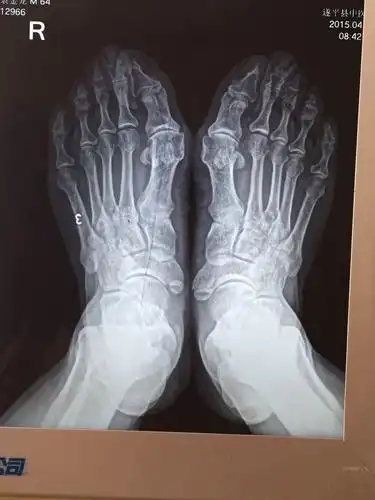

大脚骨病的微创手术